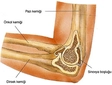

İt dirseği, genellikle dirsek ekleminde oluşan bir deformiteyi tanımlamak için kullanılan bir terimdir. Bu durum, genellikle aşırı kullanım, travma veya artrit gibi etkenlerle ortaya çıkar. İt dirseği ameliyatı, bu tür sorunları düzeltmek amacıyla uygulanan cerrahi bir müdahaledir. Bu makalede, it dirseği ameliyatının riskleri ve sonrasındaki iyileşme süreci üzerinde durulacaktır. İt Dirseği Nedir?İt dirseği, tıbbi literatürde "olekranon bursiti" olarak bilinir ve dirsek bölgesindeki bursanın iltihaplanması ile karakterizedir. Bu durum, genellikle aşırı yüklenme veya yaralanmalar sonucunda ortaya çıkar. Belirtileri arasında ağrı, şişlik ve hareket kısıtlılığı yer alır. İt Dirseği Ameliyatının Nedenleriİt dirseği ameliyatının yapılma nedenleri şunları içermektedir: